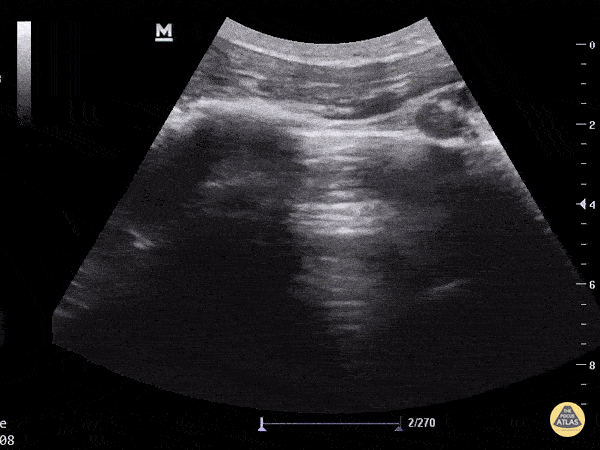

Normal lung sliding becoming more visible with decreased gain. Aaron Inouye - @PAintheED

https://www.thepocusatlas.com/lung